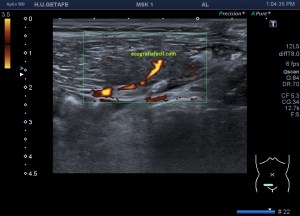

Una de ellas, la primera, era mucho más hiperecogénica y más pequeña, su centro estaba mas calcificado, su sombra acústica posterior era mucho más acuciada y llamaba más la atención. Justo al lado, otra lesión de mayor tamaño, su calcificación era mucho más sutil y más periférica delimitando una LOE hipoecogénica de un tamaño muy importante, adyacente a la más pequeña, como he comentado previamente. Ambas sin señal Doppler.

La LOE es de aspecto redondeado, heterogéneo, con multitud de pequeñas imágenes anecoicas e hipoecogénicas, de diferentes tamaños. Esta lesión fue estudiada también mediante otra técnica de imagen, la RMN donde se observa una imagen hiperdensa, con una amalgama de lesiones bordeando a periferia de la misma, de distintos tamaños como se objetiva en la imagen del mismo paciente, de la ecografía inmediatamente superior (Imagen 7). La lesión es activa, por tanto debió de ser tratada, la patología es potencialmente mortal en caso de que el quiste se rompiese.